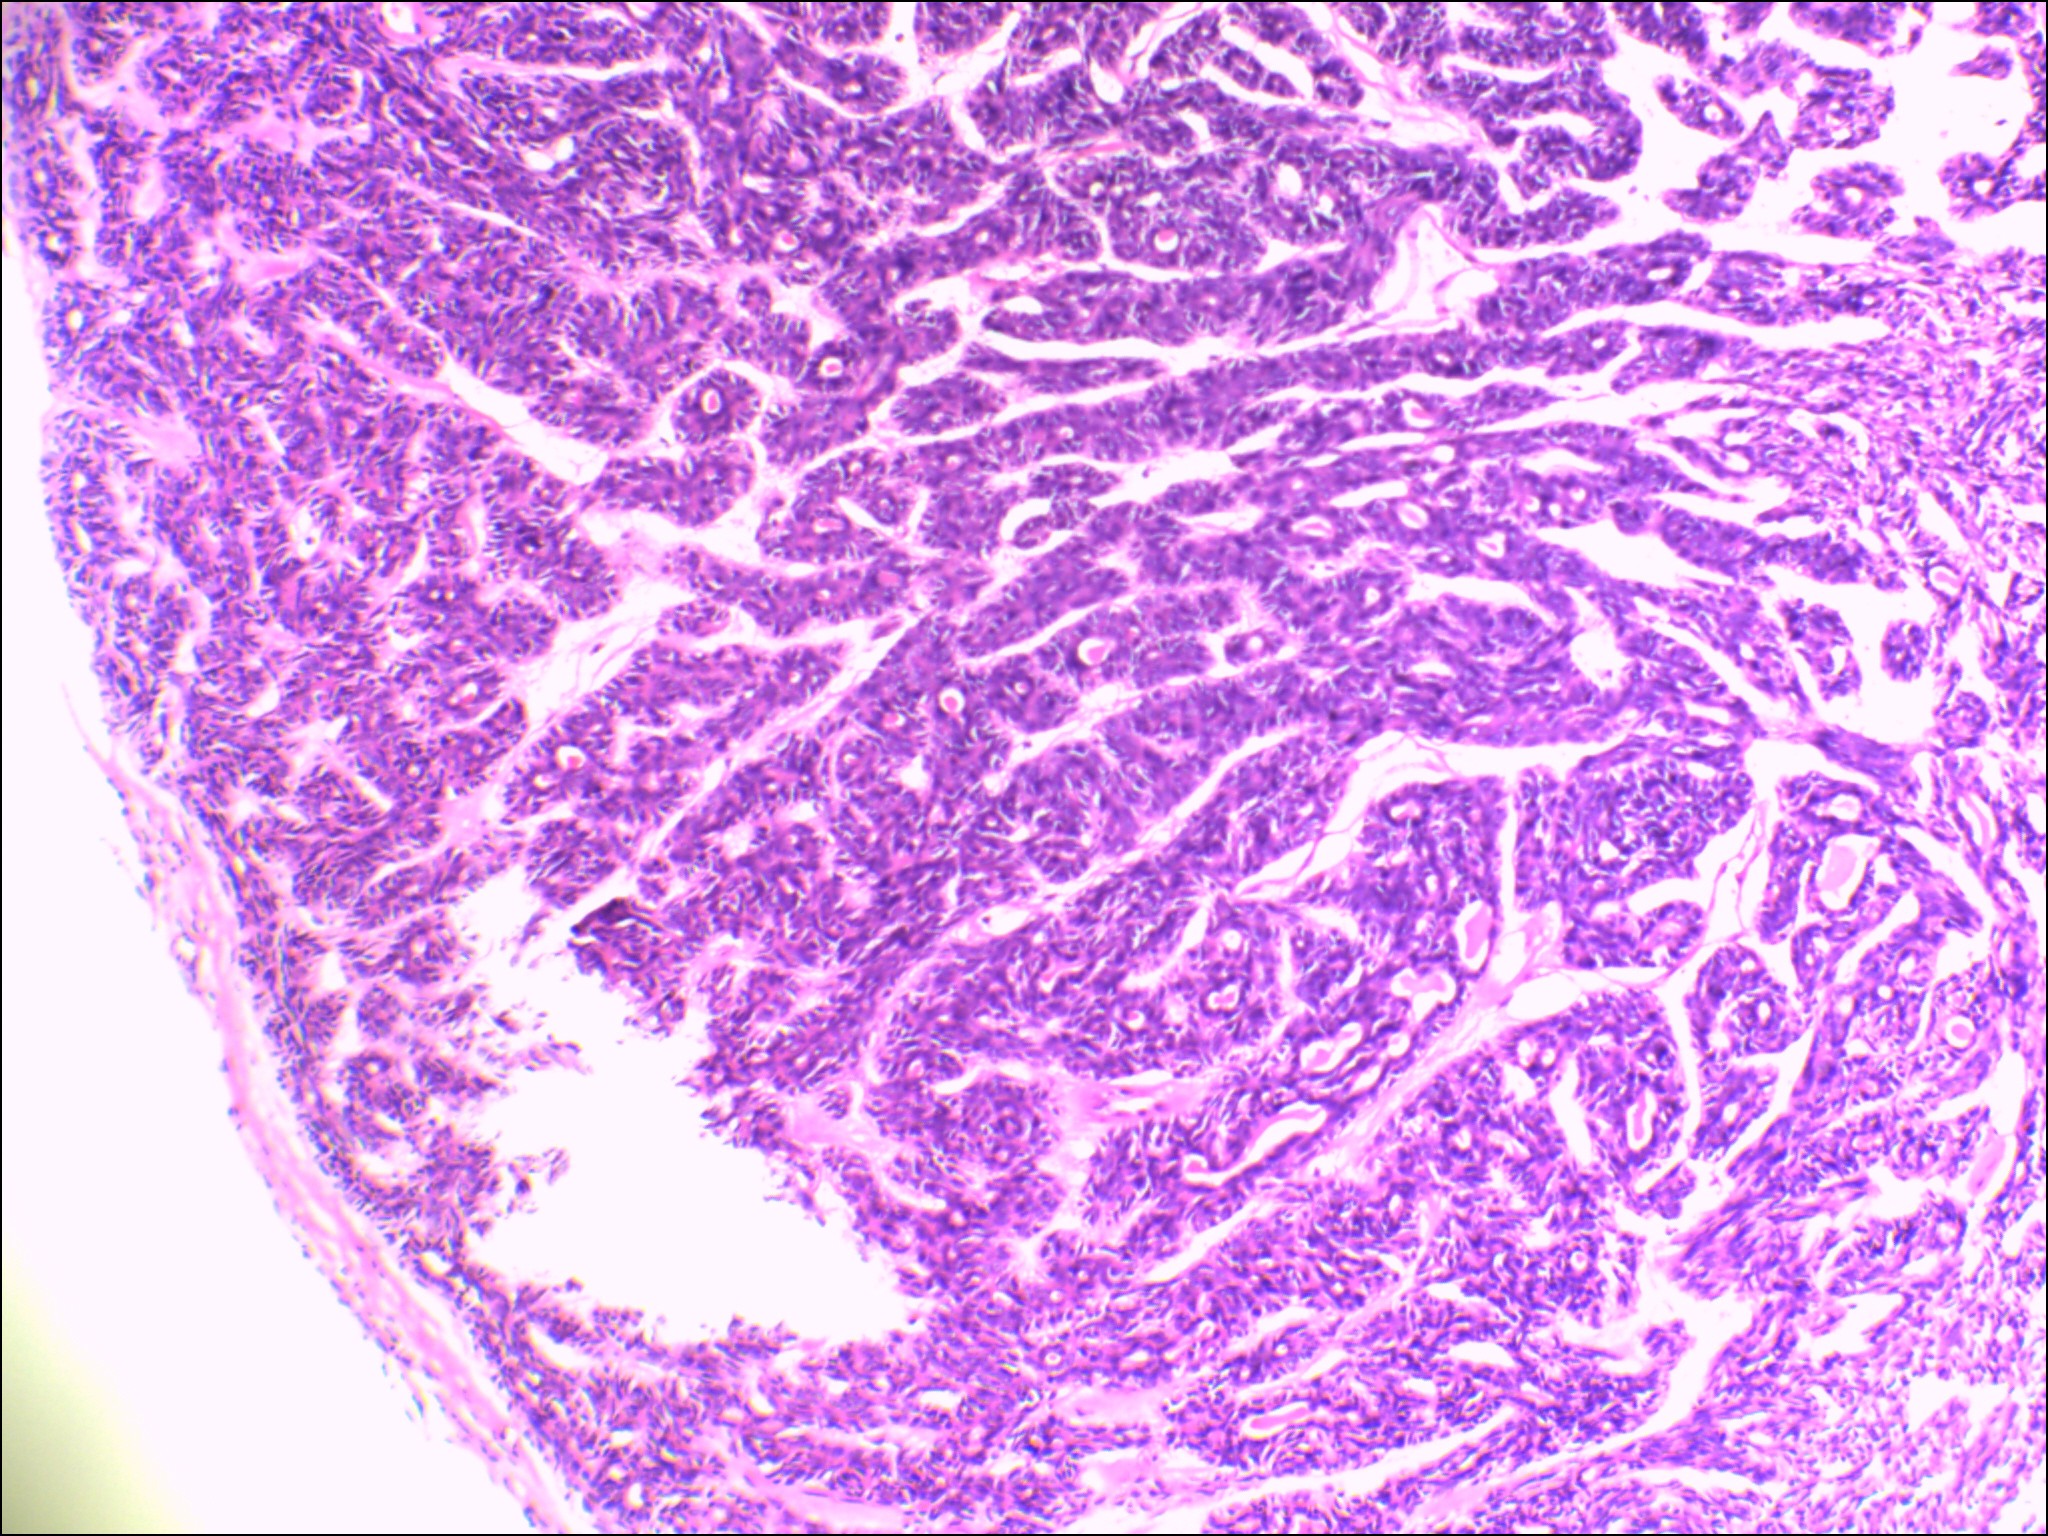

左侧腮腺肿物

性别

女

年龄

48岁

发现颈部肿块20余年

肿块大小:4×3×2.8cm,表面光滑,有包膜,切面灰白色,质硬。

图1

首先考虑基底细胞腺瘤。